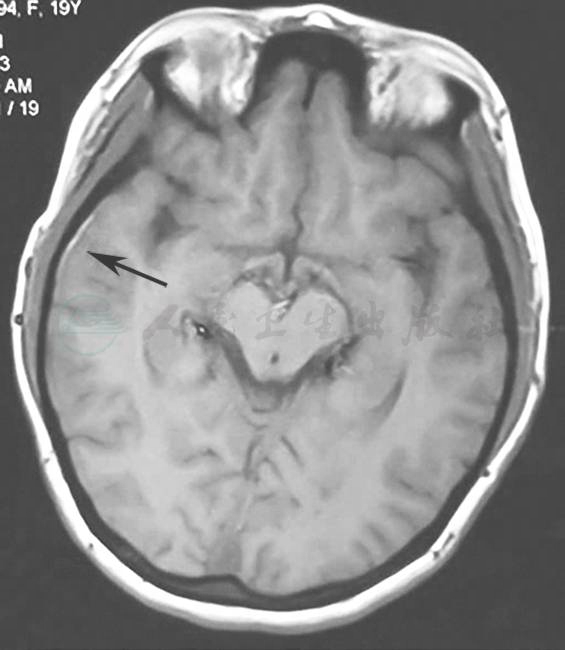

颈动脉CT示双侧颈动脉重度狭窄,颅内椎体动脉侧支循环大量形成;头颅磁共振示蛛网膜下腔出血(图2);检眼镜示左眼视网膜中央静脉阻塞;荧光素眼底造影术(FFA)示视神经萎缩;数字减影血管造影(DSA)示双侧颈内动脉远端大脑中动脉和大脑前动脉近端闭塞,代之以烟雾状细小血管(图3),双侧颈总动脉及颈外动脉通畅。

图2 头颅磁共振

黑色箭头指示T1序列右侧颞叶边缘高信号,可疑蛛网膜下腔出血